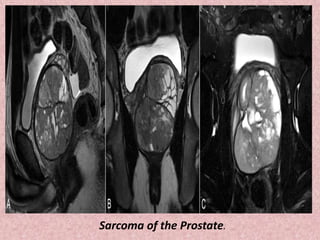

Prostatic sarcoma is an uncommon and heterogenous

group of tumour arising from mesenchymal cells in and around the

prostate.

In children the most common tumour type is a prostatic

rhabdomyosarcoma, which accounts for approximately a third of all

prostatic sarcomas .

In adults leiomyosarcomas are most common, accounting for

approximately a quarter of all cases . Many other sarcomas have

been reported although in general they are rare.

Overall prostatic sarcomas include:

rhabdomyosarcoma : most common in children

leiomyosarcoma : most common in adults

sarcomatoid carcinoma

malignant fibrous histiocytoma

phyllodes tumour (also known as cystosarcoma phyllodes of the

prostate)

undifferentiated stromal sarcoma

Sarcoma of the Prostate.

Prostate sarcoma.